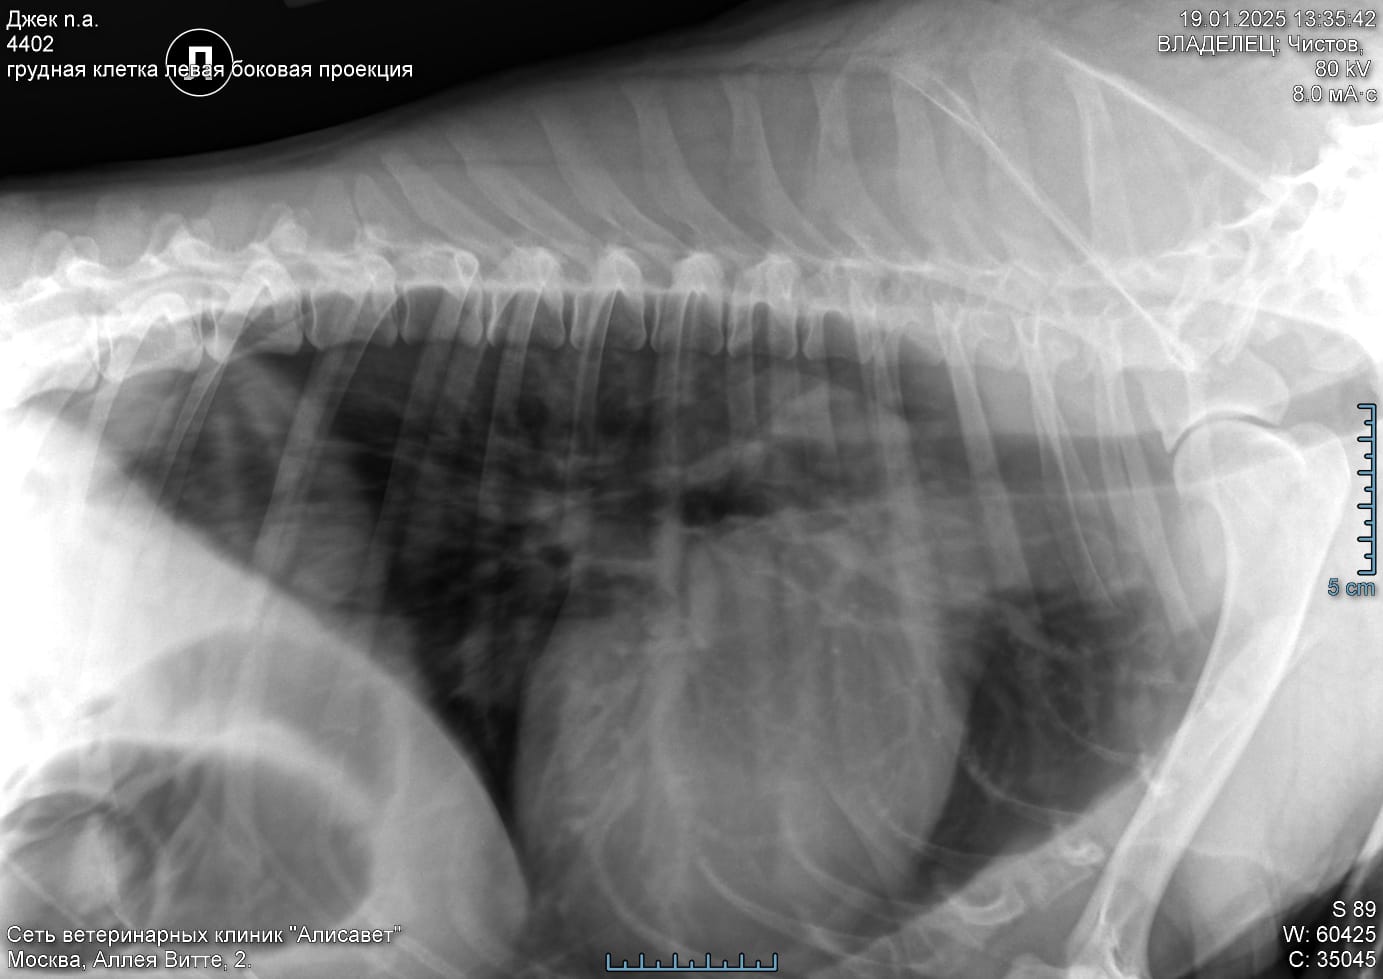

По сердцу и легким отводов нет